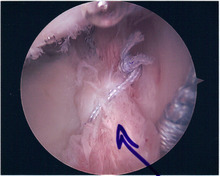

SLAP Tear

Arthroscopic SLAP Lesion (type 2) repair

Following inspection and determination of the extent of injury, the basic labrum repair is as follows.

• The glenoid and labrum are roughened to increase contact surface area and promote re-growth.

• Locations for the bone anchors are selected based on number and severity of tear. A severe tear involving both SLAP and Bankart lesions may require seven anchors. Simple tears may only require one.

• The glenoid is drilled for the anchor implantation.

• Anchors are inserted in the glenoid.

• The suture component of the implant is tied through the labrum and knotted such that the labrum is in tight contact with the glenoid surface.